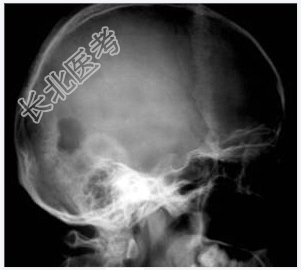

- [材料题] 病历摘要:男性,20岁。

主诉:发现头皮软组织肿物3个月。

现病史:三月前发现左枕部软组织轻微突起伴隐痛,到当地医院检查发现左枕部颅骨骨质缺损,未作具体治疗,现觉头皮肿物增大,时伴有气促、头痛。

专科检查:左颞枕部软组织略膨起,较软,各项病理反射(-)。

- 简答题1、诊断及诊断依据是什么?